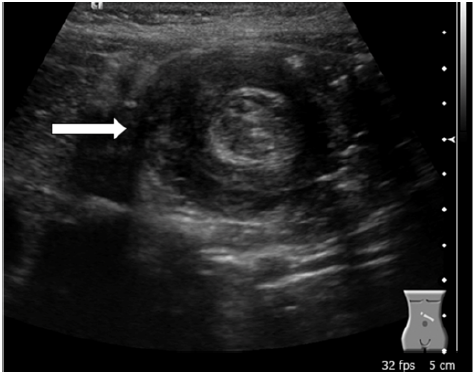

Certo lactente de 1 mês de vida, caucasiano, nascido a termo, com Apgar = 09/10, PN = 3520 g, após o 15º dia de vida, começou a apresentar vômitos não biliosos depois das mamadas, associados a irritabilidade. Foi admitido no hospital por causa de desidratação intensa em razão da persistência dos vômitos. Ao exame físico do abdome, constataram-se hiperperistalse gástrica (ondas de Kussmaul), distensão do andar superior abdominal e oliva palpável adjacente à loja vesicular. O restante do exame físico mostrou-se sem alterações.

Tendo em vista essas informações, a principal hipótese diagnóstica é

Uma menina de 10 meses de vida foi levada ao departamento de emergência com vômitos persistentes, letargia, distensão abdominal e choro inconsolável. Optou-se então, pela realização de exames laboratoriais e de uma ultrassonografia de abdome total. Com base na imagem apresentada, qual é a principal patologia?